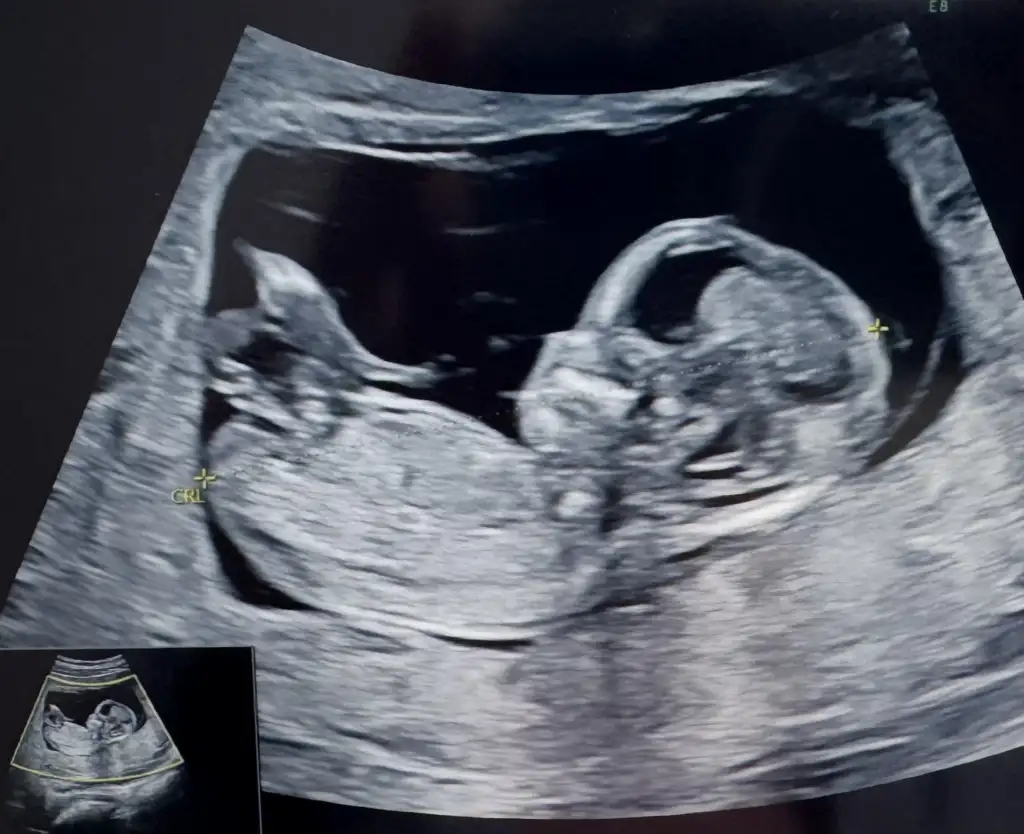

Kiza benzettim ama erkege de benzettim yamerhaba bugün tam 13hafta cinsiyet tahmininiz var mıEki Görüntüle 3619011 Eki Görüntüle 3619012 Eki Görüntüle 3619013